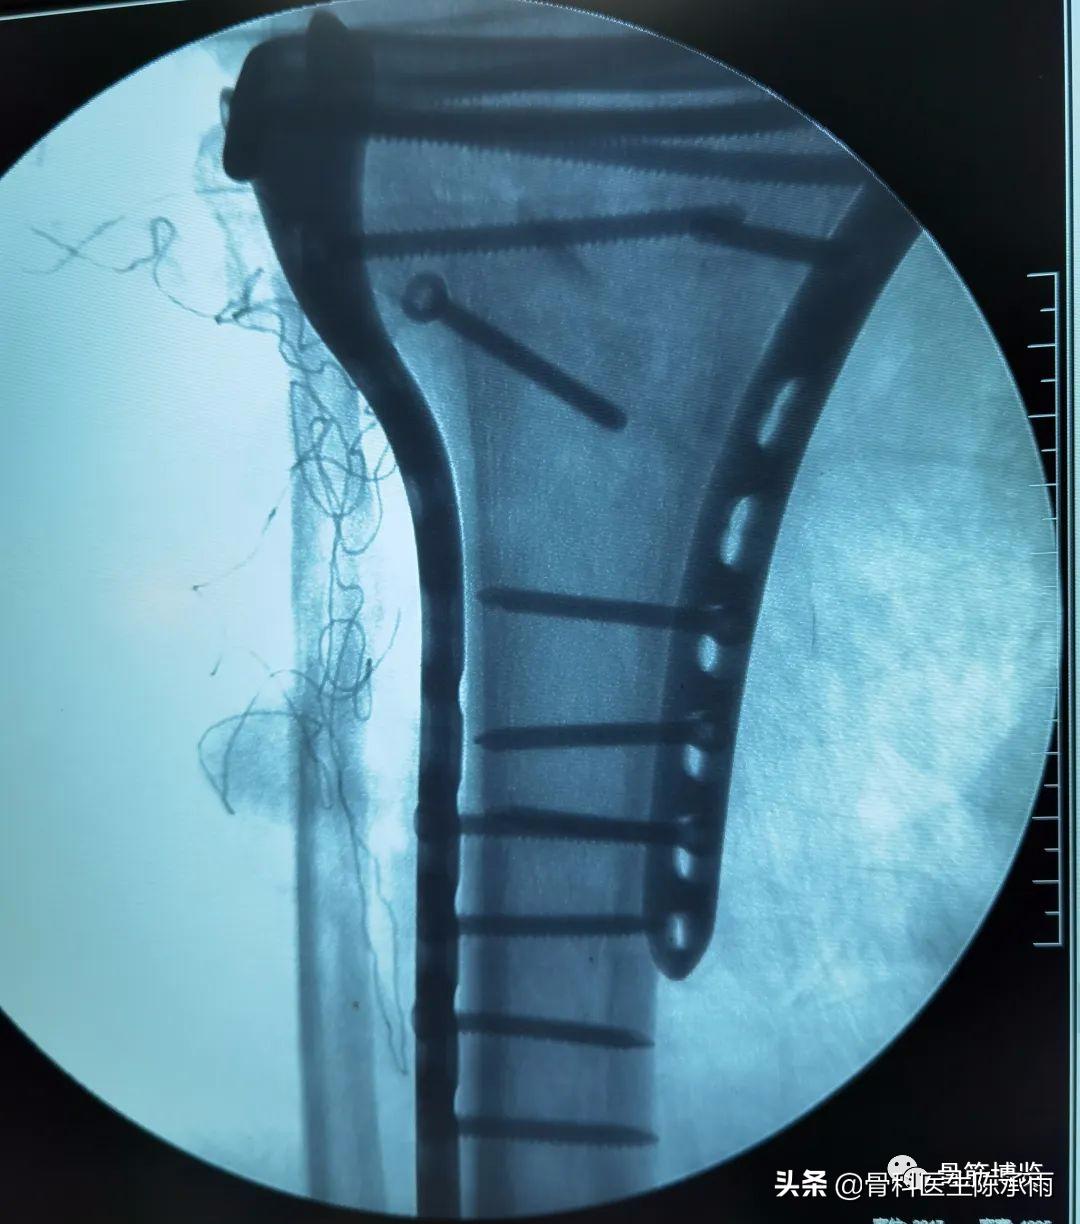

这2例患者皮肤条件差,全身多发骨折,小腿皮肤条件差,1例筋膜高压切开,1例整个小腿布满张力性水泡,胫骨骨折都在伤后30天才能手术。

下例胫平台骨折皮肤条件差,内侧板取两端小切口置入内板固定。胫骨结节处撕脱骨折以1枚拉力螺钉固定。